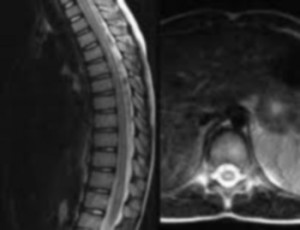

- MRI (magnetic resonance imaging): Provides images of the brain and spinal cord so that lesions can be identified.